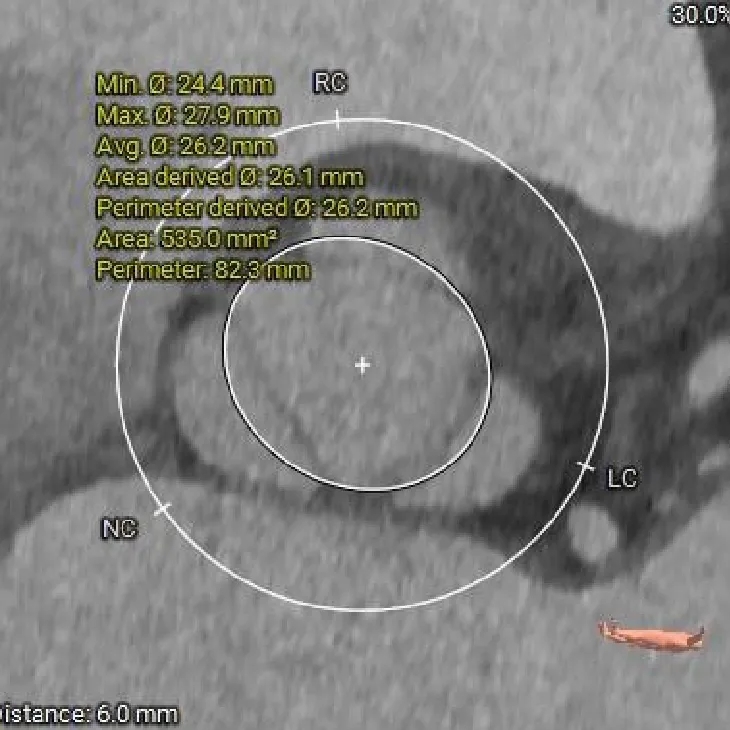

术前CT分析

主动脉根部测量

Annulus

26.6mm

LVOT

27mm

SOV

40.2*39.3*38mm

STJ

36.7mm

AAO

38.8mm

心脏角度

纯反流三叶瓣,瓣环内径26.6mm

流出道偏直筒型

瓣叶轻微增厚、无钙化

57°,近似横位心

瓣上结构测量

瓣上2mm

27.3mm

瓣上4mm

29mm

瓣上6mm

30.1mm

瓣上8mm

31.1mm

瓣上锚定空间逐渐增大,仅瓣上0-2mm可提供锚定力